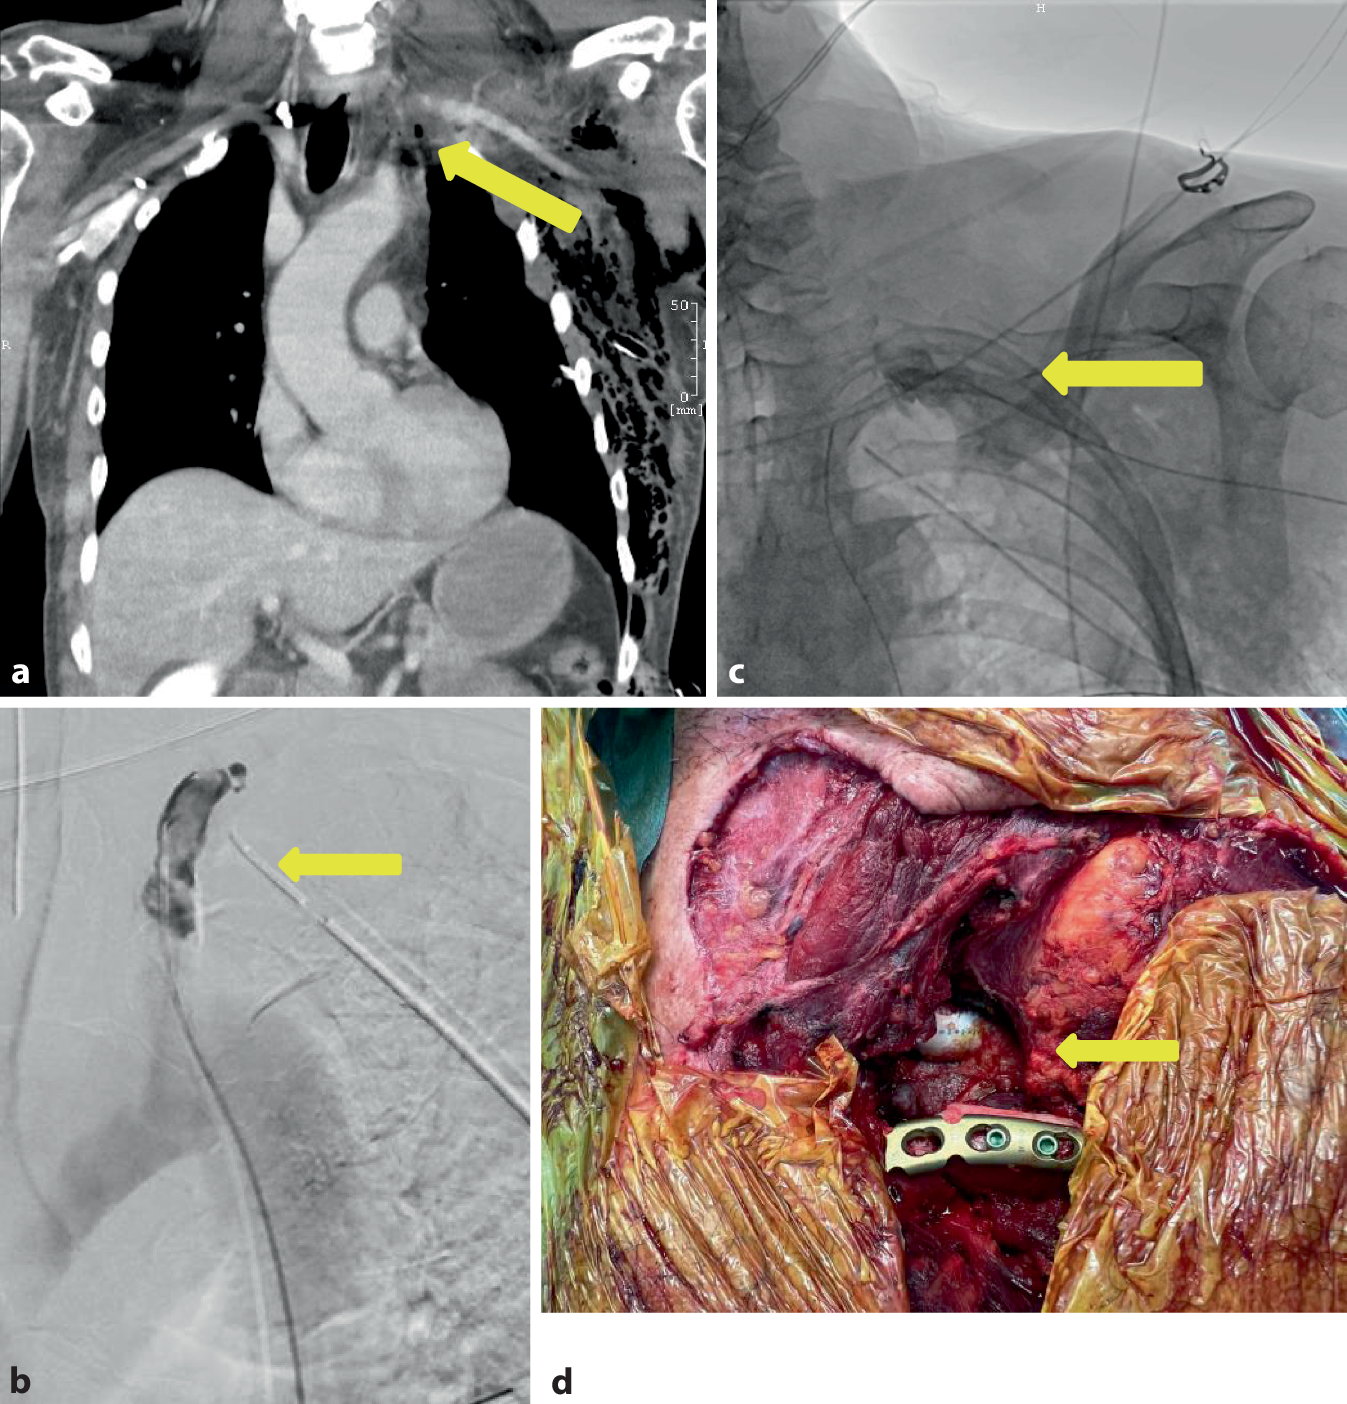

Der 60-jährige Patient fuhr mit seinem PKW in den Abendstunden ungebremst auf ein stehendes Fahrzeug auf und zog sich eine penetrierende Verletzung der A. subclavia links im Bereich des Abganges der A. vertebralis links mit akuter Ischämie des linken Armes, einem großen Haut-Weichteil-Defekt im Bereich des linken unteren Halsdreiecks mit Abriss des M. sternocleidomastoideus, eine drittgradig offene Klavikulafraktur links mit ausgeprägtem supra- und infraklavikulärem Hämatom, ein Emphysem und einen Hämatopneumothorax links bei Rippenserienfraktur links und eine offene Unterkieferfraktur links zu. Die CTA zeigte kurz hinter dem Abgang aus der Aorta einen Verschluss der A. subclavia links über eine Länge von ca. 5 cm im Bereich der bestehenden Klavikulafraktur (Abb. 4a). Bei stabilen Kreislaufverhältnissen entschied man sich zum Versuch der interventionellen endovaskulären Rekanalisation des Subklaviaverschlusses (Abb. 4b, c). Dieser ließ sich jedoch nicht sondieren und versorgen, sodass bei fortgeschrittener Ischämiezeit des Armes zeitnah die Indikation zur offenen Revaskularisation gestellt wurde. Intraoperativ zeigte sich das Bild einer langstreckig mazerierten A. subclavia mit langstreckiger intravasaler Dissektion und multiplen thrombosierten Intimadefekten, die in den Abgangsbereich der A. vertebralis, A. mammaria, Truncus thyreocervicalis und Truncus costocervicalis reichte. Es wurde die aufwendige Intimarekonstruktion und nachfolgende Patchplastik mit einem XenoSure® Patch (Le Maitre Vascular, Burlington/VT, USA) zum Erhalt der Gefäßabgänge durchgeführt. Bei sich weiter fortsetzender Dissektion nach zentral mit thrombotischem Verschluss erfolgte nach zentral die Ligatur der A. subclavia und Anlage eines karotidosubklavialen Bypasses mit einer beringten Polytetrafluorethylen(PTFE)-Prothese (Gore Propaten®, 8 mm, W. L. Gore & Associates, Inc., Putzbrunn, Deutschland) mit distalem Anschluss auf die Patchplastik (Abb. 4d). Im Anschluss erfolgte die Versorgung der Klavikulafraktur mit einer winkelstabilen Platte. Aufgrund der überlangen Ischämiezeit erfolgte die prophylaktische Kompartmentspaltung am Arm. Die Aa. radialis und ulnaris waren klinisch unmittelbar nach Rekonstruktion kräftig tastbar und mit dem „Hand-Doppler“ ableitbar.

Abb. 4

Fall 4: Traumatische Verletzung der A. subclavia links. a CT-Angiographie mit Nachweis des Verschlusses der A. subclavia links (gelber Pfeil), b Angiographie mit Versuch der Sondierung des Verschlusses vom Abgang aus der Aorta (gelber Pfeil), c Angiographie mit Sondierung des Verschlusses im Rendesvouz-Verfahren zusätzlich von transbrachial (gelber Pfeil), d Operationssitus mit sichtbarer PTFE-Prothese und rekonstruierter Klavikula mit Platte (gelber Pfeil)